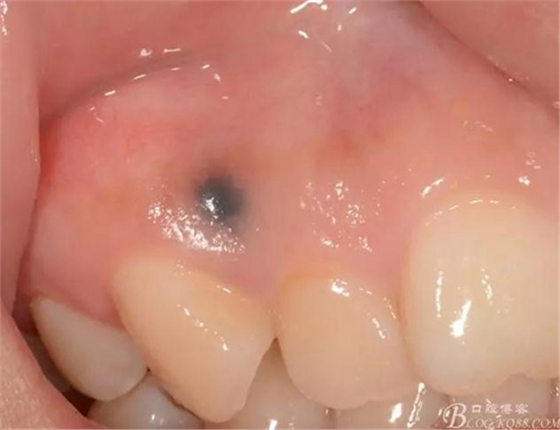

初診日期:2015-09 女孩很漂亮,來診要求洗牙,但是我發(fā)現(xiàn)女孩愛笑,但是總是用手刻意的擋著嘴,后來才發(fā)現(xiàn)是因?yàn)檠例l上有個(gè)“黑點(diǎn)”

主訴:牙齦上黑色素沉著十年有余

現(xiàn)病史:患者自述幼時(shí)鋼筆戳傷牙齦后,墨水沉積在牙齦內(nèi),現(xiàn)自覺不美觀,要求診治

檢查:口腔衛(wèi)生尚佳,軟垢少量,牙石(+),色素沉著少量,全口牙齦色粉,質(zhì)地韌,BOP(+-),BI=0-1,全口PD=1-3mm左右,12,13唇側(cè)附著齦根尖方向處可見圓形色素沉著區(qū)(墨水沉積所致),其余黏膜以及唇紅未見異常,全口牙列未見明顯齲損。

術(shù)前